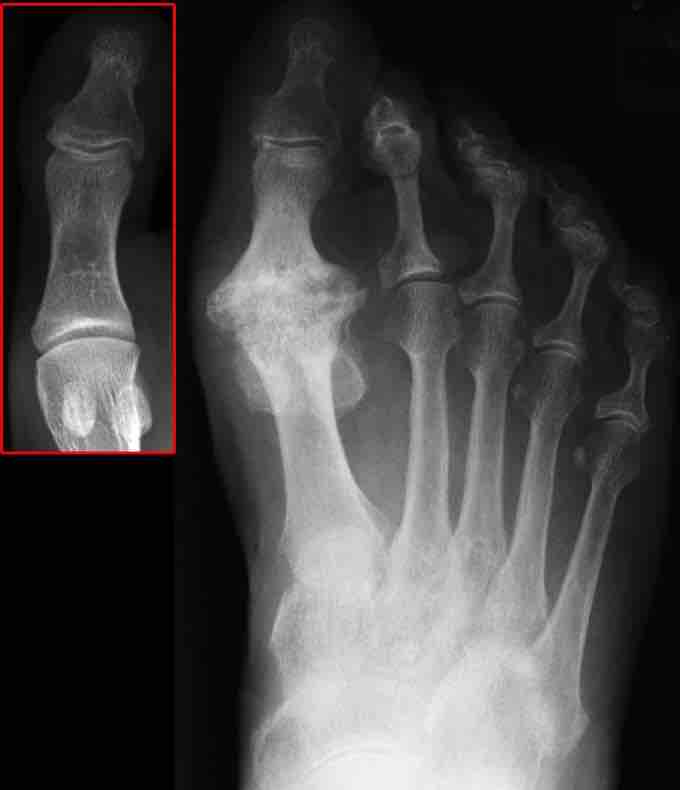

Osteoarthritis

X-ray image of osteoarthritis of the big toe. The red box shows the normal joint.